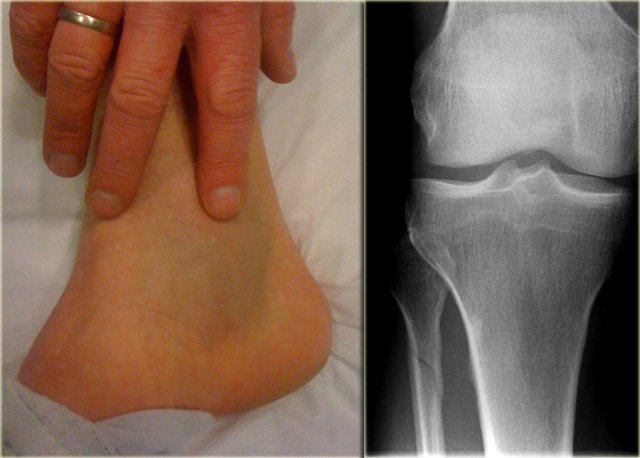

Example 1

On the left images of a patient with a hematoma on the medial side.

• First impression

We can exclude a Weber A or B fracture, because we see no fracture.

A high Weber C is still a possibility, i.e.

• medial ligament rupture

• high fibular fracture

• posterior syndesmosis rupture.

• Re-examination

Additional radiographs of the lower leg were taken and demonstrated a high fibular fracture, also known as Maisonneuve fracture.

• Final report

Weber C stage 4, i.e. medial collateral ligamentous rupture, rupture of the anterior syndesmosis, high fibular fracture and probably a rupture of the posterior syndesmosis.

Teaching point No fracture on the radiographs of the ankle does not exclude an unstable ankle injury

This case demonstrates that there can be an unstable ankle injury that needs surgery even when the radiographs of the ankle do not show a fracture.